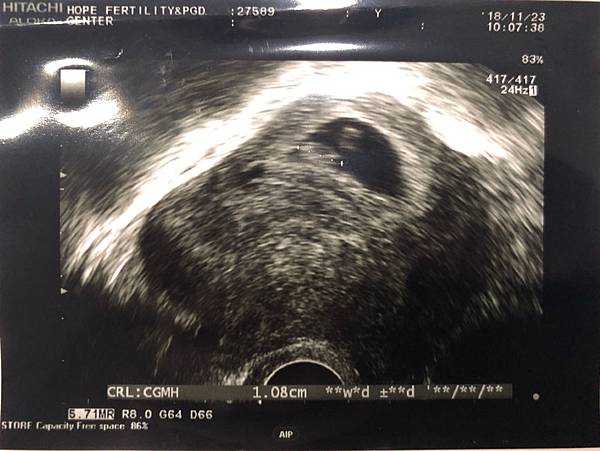

IG常分享凱開和我們生活的日常,歡迎追蹤,點⬇️連結 : https://www.instagram.com/deb.c.shen/———— 11/23 7W3D ————

又到了每週的回診時刻,今天超音波顯示還是有點在出血,但寶寶有健康的長大,現在週數還太小,還看不出頭和身體,醫生告知大概在1週就可以清楚的看到囉。雖然沒有出血的症狀,但因為超音波下還是有出血,所以黃體油針需要繼續打,醫生交代千萬不能太累,要盡量休息。有告知醫生我有孕吐和脹氣的症狀,因為沒有嚴重到影響健康,所以不會打止吐針,只先開立最基本的B6,希望能緩解。